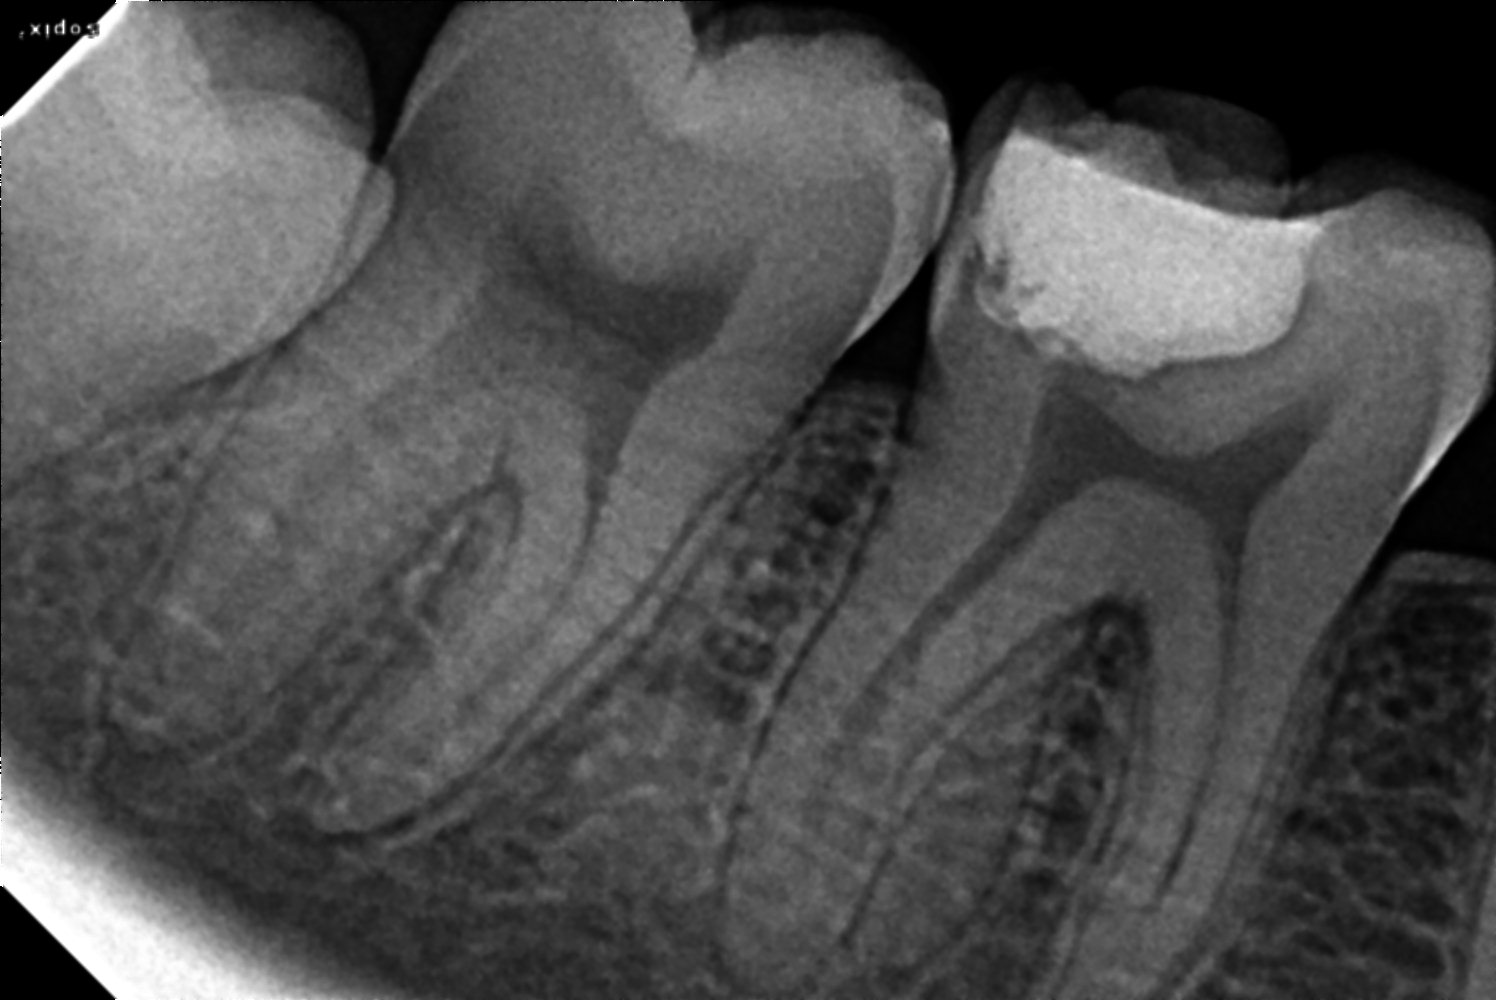

Treatments46 rct done

bioseramic sealer

radix